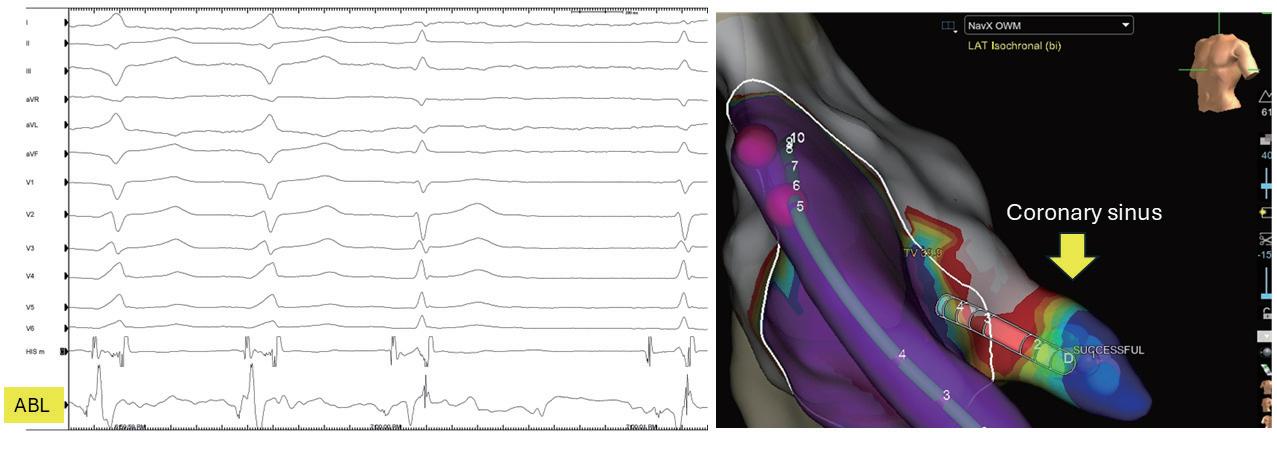

一名 28 歲男性因長期慢性鼻塞,計畫進行手術住 院。然而,術前心電圖檢查意外發現患者有 WolffParkinson-White (WPW) 症候群,心律呈現sinus rhythm 並伴隨 Ventricular Pre-excitation 。根據 Maximum Preexcitation Algorithm1的分析 (如圖一),顯示其accessory pathway位於right paraseptal area。患者自述偶有心悸及 胸悶等症狀,因異常心電圖結果,手術暫停並轉診至 心臟科進一步評估。後續進行運動心電圖及 24 小時 Holter ECG 檢查,未發現或誘發上心室頻脈。為進一

步確認診斷,患者住院接受電生理學檢查 (EPS)。檢查 中成功誘發orthodromic AVRT,結果顯示accessory pathway 位於心室後中膈,並於冠狀靜脈竇 (coronary sinus) 近 端開口內以射頻電燒成功消除 ( 如圖二 ) 。診斷確立為 Coronary Sinus-Ventricular Accessory pathway。術後追 蹤心電圖未再發現Ventricular Pre-excitation (如圖三)。 患者門診持續追蹤,未再出現心悸復發,整體恢復良 好。

(圖一)、左圖為病人電燒前12導程心電圖,如根據右圖Maximum Pre-excitation Algorithm, accessory pathway在right paraseptal area。

(圖二)、accessory pathway位於心室後中膈並於冠狀靜脈竇 (coronary sinus) 近端開口內記錄到 fused atrial and ventricular electrogram,電燒後體表心電圖pre-excitation消失且局部 atrial and ventricular electrogram分開。